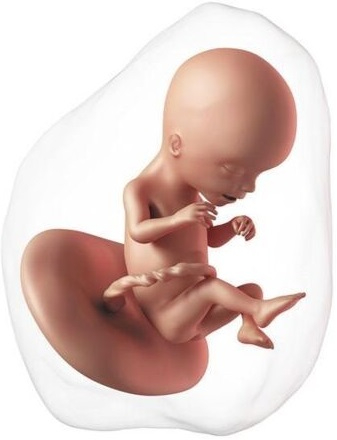

El proceso de la formación del embrión está ya prácticamente finalizado con una longitud de 30 mm. A partir de ahora empieza la etapa fetal, médicamente ya no es un embrión sino un feto. Ya ha completado la formación básica de todos los sistemas.

Ahora ya se mueve con frecuencia, pero son movimientos involuntarios; los músculos todavía tardarán en estar conectados con el cerebro. La cabeza es mucho más grande que el cuerpo, ya tiene orejas, nariz, hasta los párpados, los cuales estarán fusionados durante semanas. Los labios están formados y empieza a abrir la boca. Ya han aparecido pies y manos.

En esta etapa los genitales son exactamente iguales en niños y niñas. Tienen un tubérculo genital que más adelante se diferenciará en la forma de cada sexo. Su piel es translúcida, se puede ver el esqueleto a través de ella. En realidad, los huesos no tienen casi calcio, están formados por cartílago, pero la mayoría de los huesos ya tienen su forma definitiva.